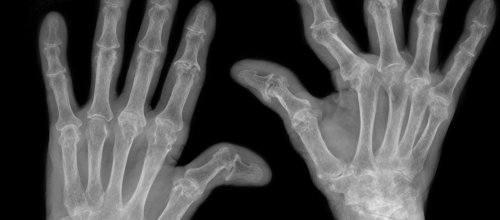

Rheuma Hände

Rheumatologie

„Wir haben eine therapeutische Revolution erlebt!"

Wer schon einmal versucht hat, einen Termin beim Kassen-Rheumatologen zu bekommen, wird entdeckt haben: Eine Einhornsichtung ist wahrscheinlicher. Denn Rheumatolog:innen sind ob der fehlenden Möglichkeit einer Verrechnung mit den Kassen fast gezwungen, in die Wahlarztpraxis zu gehen. Judith Sautner, Präsidentin der ÖGR (Österreichische Gesellschaft für Rheumatologie und Rehabilitation) und Primaria am Landeskrankenhaus Korneuburg-Stockerau, über die Stimmung in der Kollegenschaft, den Wunsch nach mehr Rheumatologie im Medizin Curriculum und das weite Feld ihres Fachs.